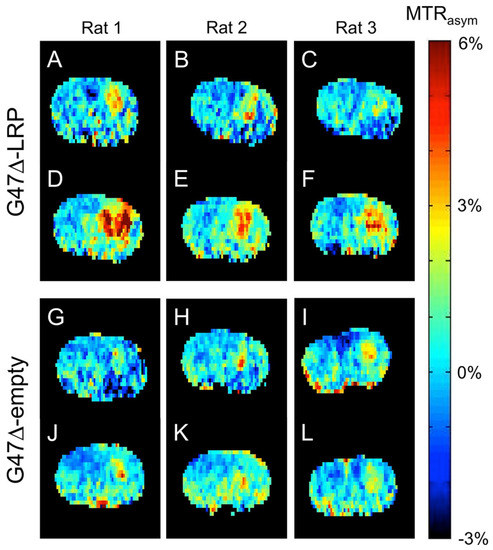

- Sagiyama, K.; Mashimo, T.; Togao, O.; Vemireddy, V.; Hatanpaa, K.J.; Maher, E.A.; Mickey, B.E.; Pan, E.; Sherry, A.D.; Bachoo, R.M.; et al. In vivo chemical exchange saturation transfer imaging allows early detection of a therapeutic response in glioblastoma. Proc. Natl. Acad. Sci. USA 2014, 111, 4542–4547. [Google Scholar] [CrossRef]

- Farrar, C.T.; Buhrman, J.S.; Liu, G.; Kleijn, A.; Lamfers, M.L.M.; McMahon, M.T.; Gilad, A.A.; Fulci, G. Establishing the Lysine-rich Protein CEST Reporter Gene as a CEST MR Imaging Detector for Oncolytic Virotherapy. Radiology 2015, 275, 746–754. [Google Scholar] [CrossRef]